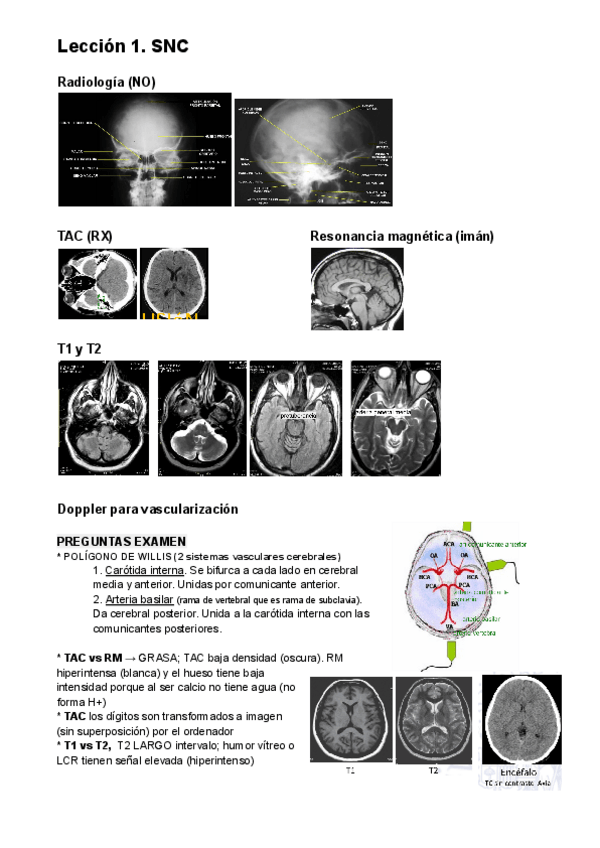

tema-1-snc.pdf